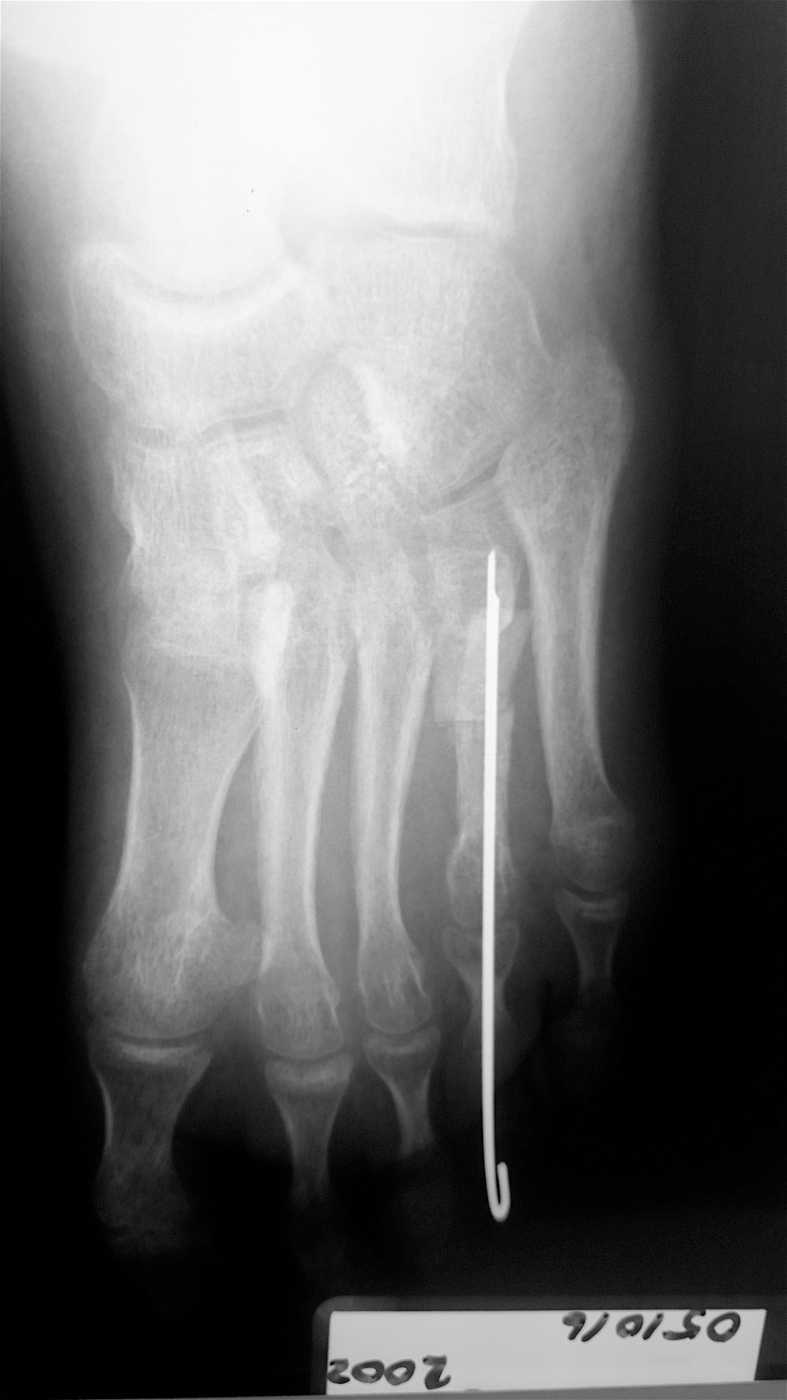

Случай брахиметатарзия, операция остеотомия с аллопластикой бикортикальным трансплантатом  "Лиопласт".